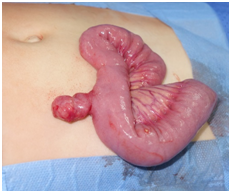

During a 11-year period, thirty-two children (29 boys, 3 girls) were enrolled in the current study.  The patients’ ages ranged from 2months to 17years (median 5years) with 6 cases with less than 2years old, 9 cases with ages between 2 and 5years old, 9 cases with ages between 5 and 9years old, and 8 cases aged 10 or more years old. The diverticular pathology was denoted by inflammatory, occlusive or bleeding phenomena. Thus of 32 cases, 14 were diagnosed as intestinal obstruction (43,8%), 12 cases presented with lower gastrointestinal bleeding (37,5%) and 6 cases showed symptoms of diverticulitis (18,8%). Among the causes of intestinal occlusion, there were 9 cases of intussusception, 3 cases of mesodiverticular band causing occlusion (by direct compression, induction of volvulus or internal hernia), one case of MD torsion and one case of adhesions from MD to cecum. With respect to major symptom, among the total of patients, abdominal pain was found in 20 cases (62,5%), while vomiting was found in 18 cases (56,2%), lower gastrointestinal bleeding was found in 12 cases (37,5%) and fever in 7 cases (21,9%) (Figures 1–4).

Figure 1 Operative photograph of Meckel Diverticulum in a patient with diverticular haemorrhage.

Figure 2 Operative photograph of Meckel Diverticulum in a patient with diverticular haemorrhage.